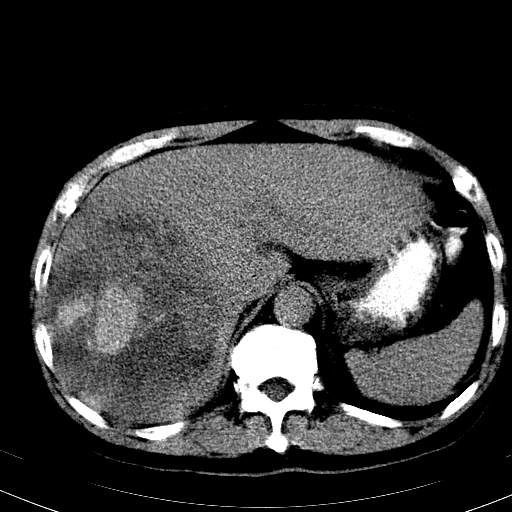

以下是引用卜一在2008-6-23 15:38:00的发言:[br]本例延时期的图象未扫完,单纯平扫 动脉期及门脉期特征分析:平扫低密度较大肿块,内见不规则出血灶,界限清楚。动脉期边缘结节样强化,门脉期病灶边缘进一步强化并范围明显缩小。因此考虑:血管瘤伴出血!